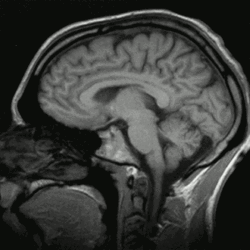

Programmation précoce

Les images par la résonance magnétique (IRM) contemporaine ont procuré un support empirique solide pour la théorie psychologique selon laquelle la programmation émotionnelle est largement définie dans l’enfance, d’autant qu’à l’âge de neuf mois le cerveau a déjà 95 % du volume qu’il aura à l’âge adulte.